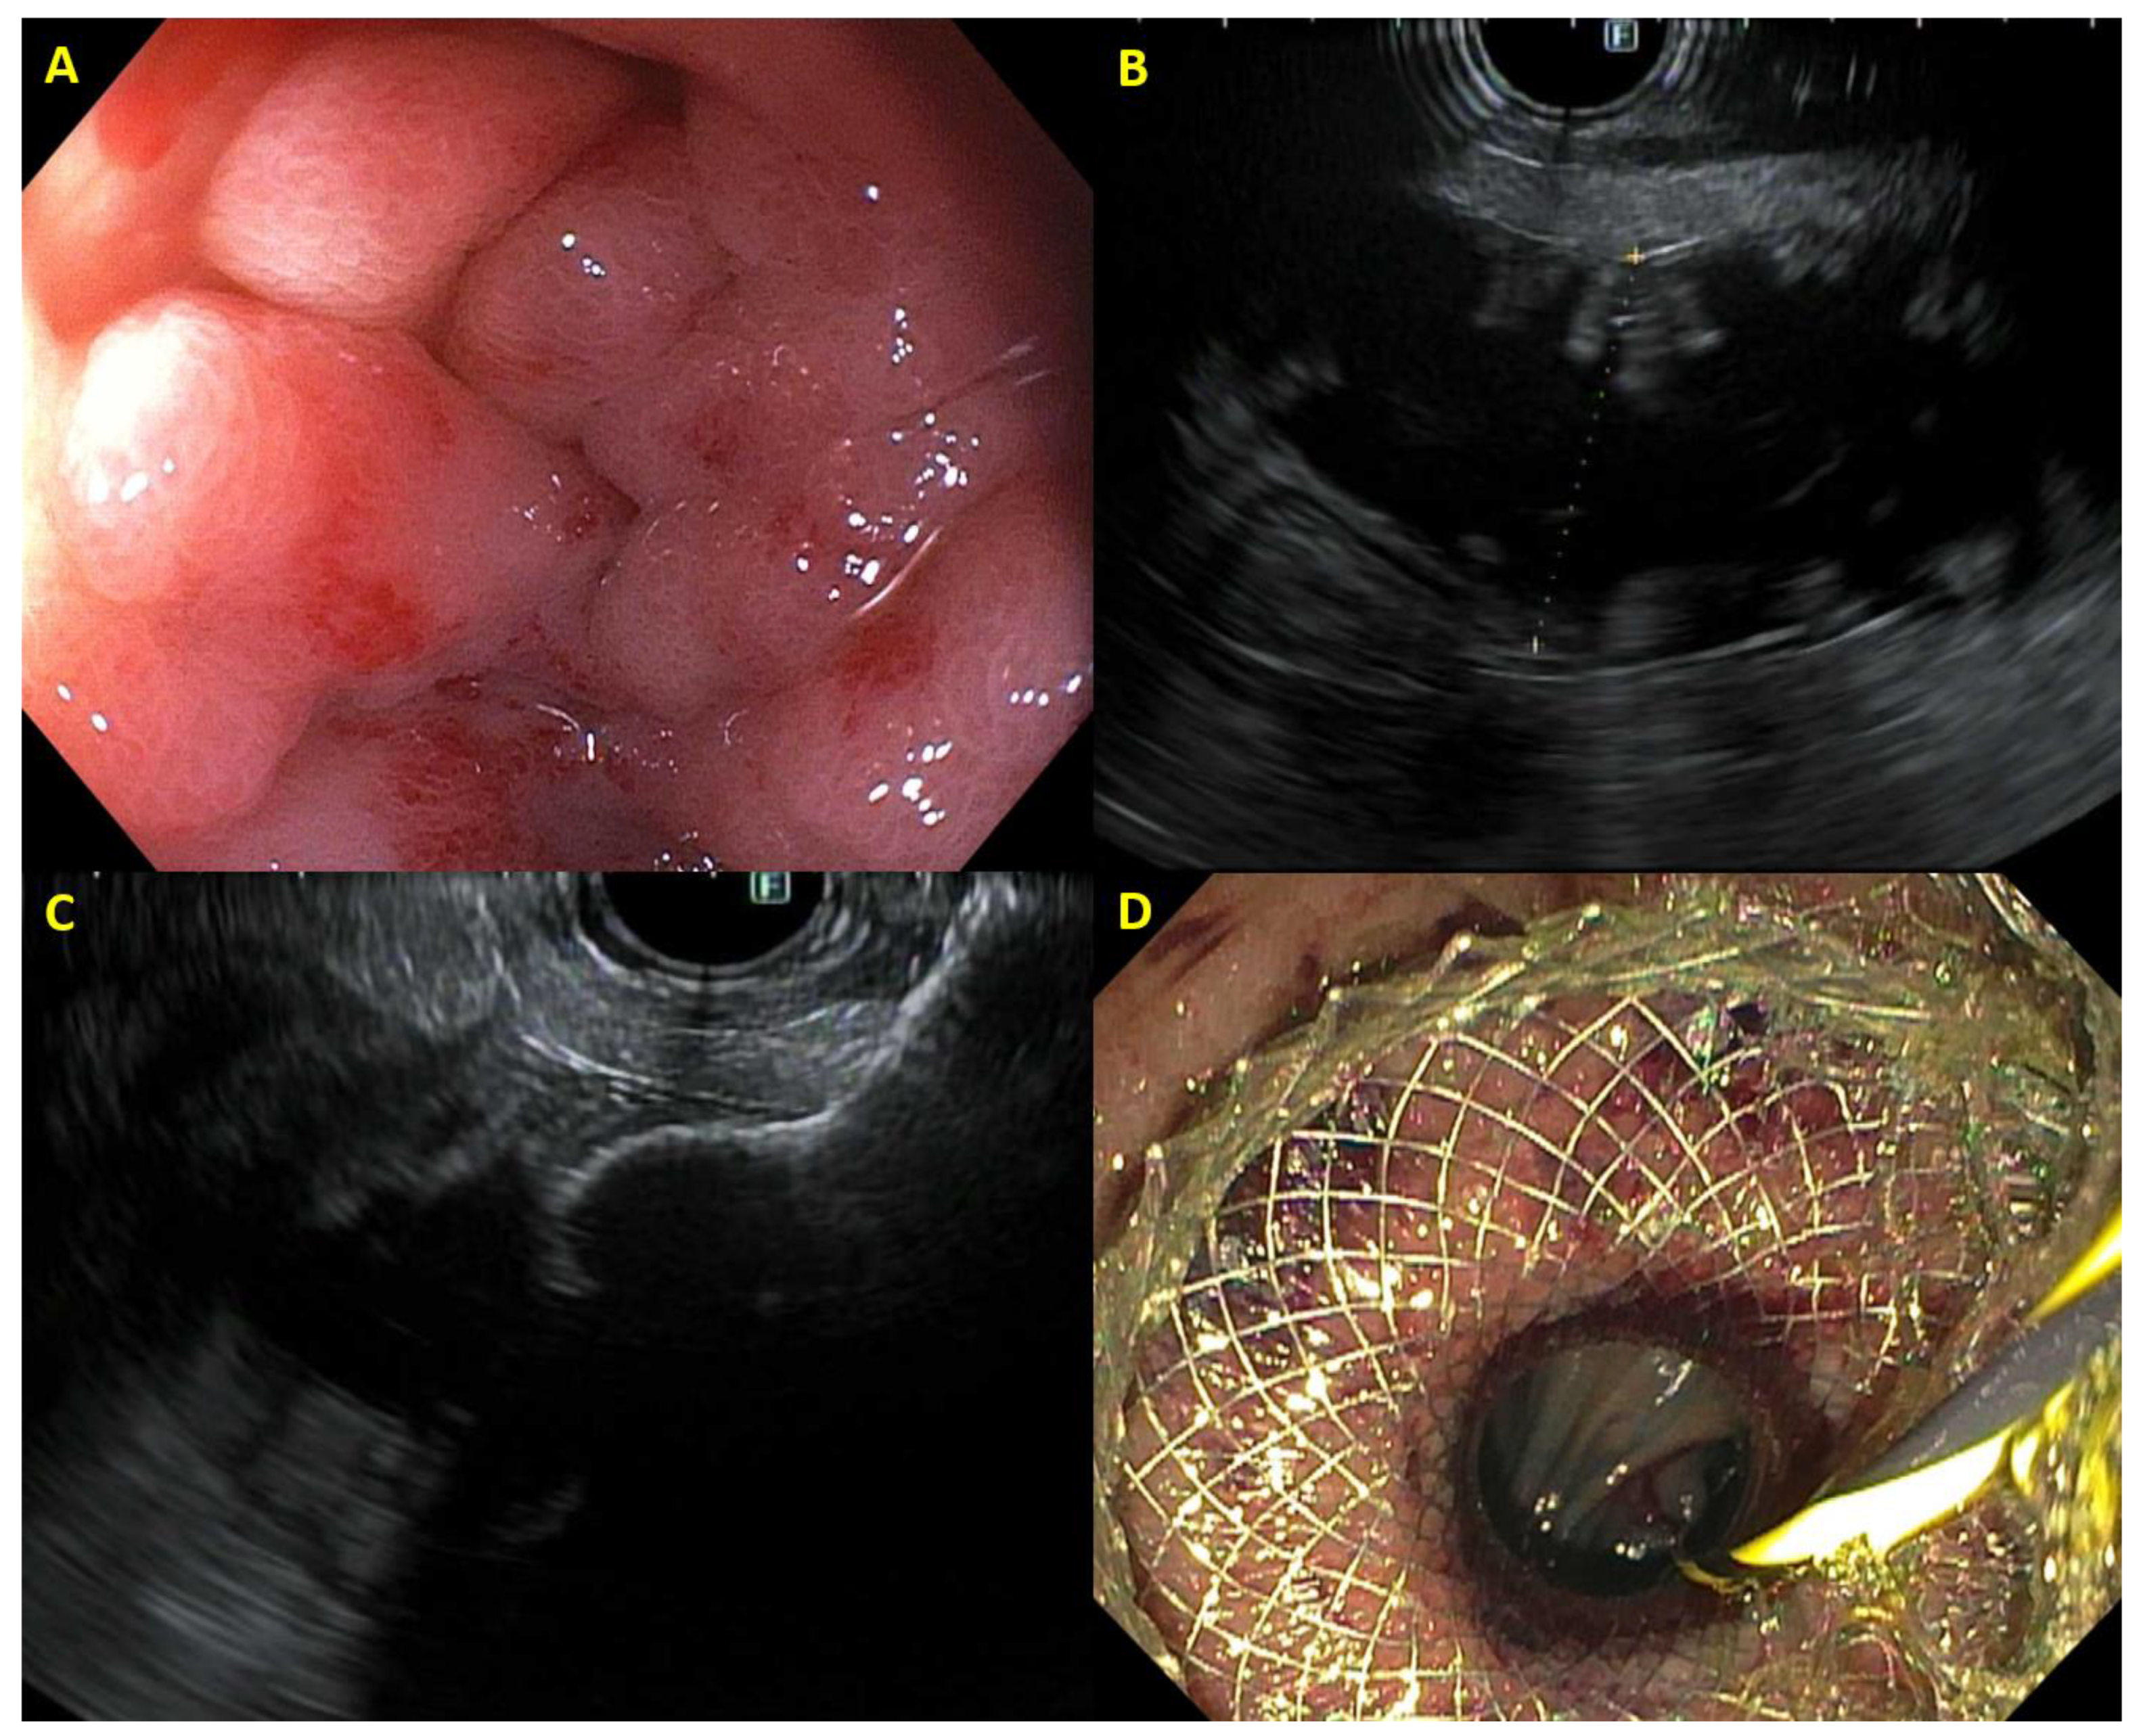

2.6. EUS-Guided Gastroenterostomy

2.7. Afferent Loop Syndrome